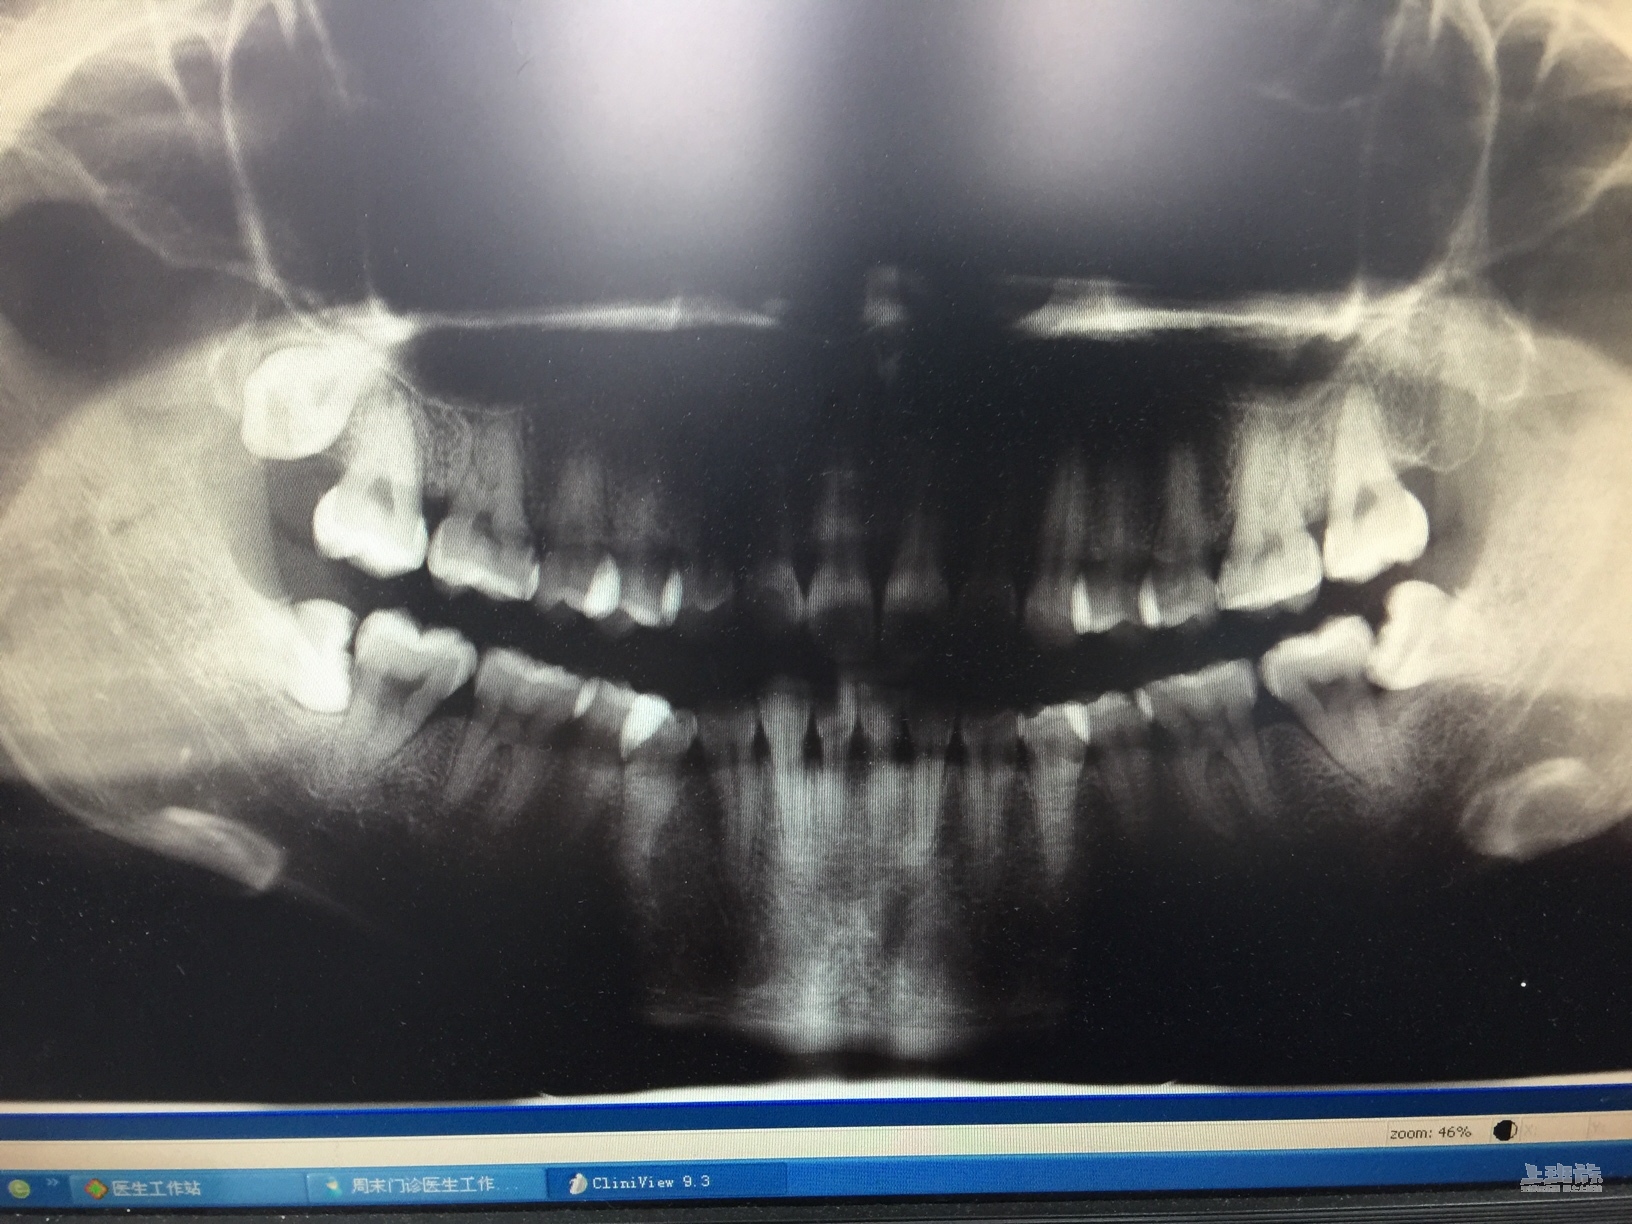

你的长得和我的一摸一样。

还有一颗和你一样躺着的。 躺着的一般没什么问题 正常长的要拔 会肿 把肉咬到

只要不发炎不痛躺着不顶牙。密封。没事。